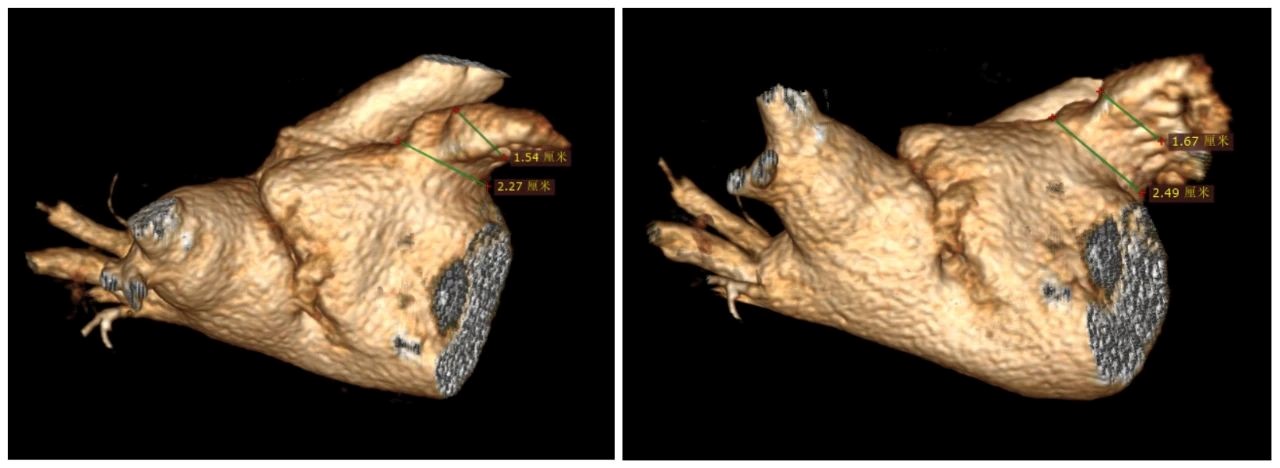

在术前评估中,陈弹主任团队通过CT建模发现患者左心房内疑似存在心房隔膜。术中通过心腔内超声进一步检查,明确了患者左心房内部的确存在心房隔膜,而心房隔膜的存在增加了术中导管操作的难度。在我院心内科电生理团队的共同努力下,房颤一站式手术顺利完成。在肺静脉隔离过程中,患者房颤心律成功转复为窦性心律。困扰了吴爷爷3年多的“心病”得以解决。

陈弹主任介绍,心房隔膜是一种少见的先天性心脏发育畸形,其发病原因多由于胚胎发育过程中共同肺静脉干退化吸收不全而残留隔膜,或者肺静脉干与左心房连接异常,也有可能与原发隔异常发育有关。